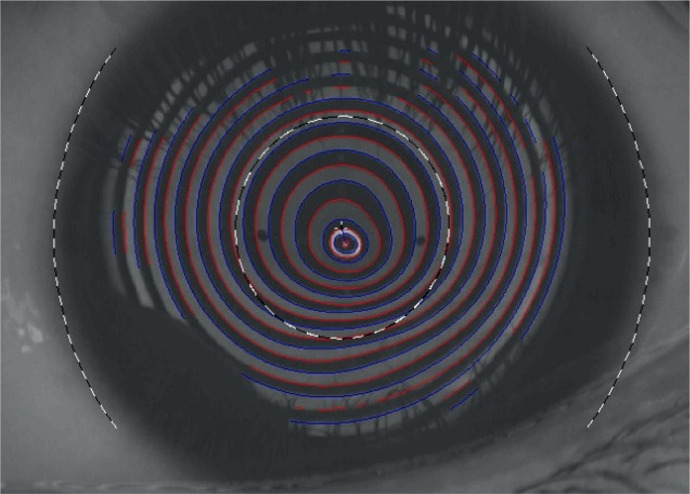

Abstract Image